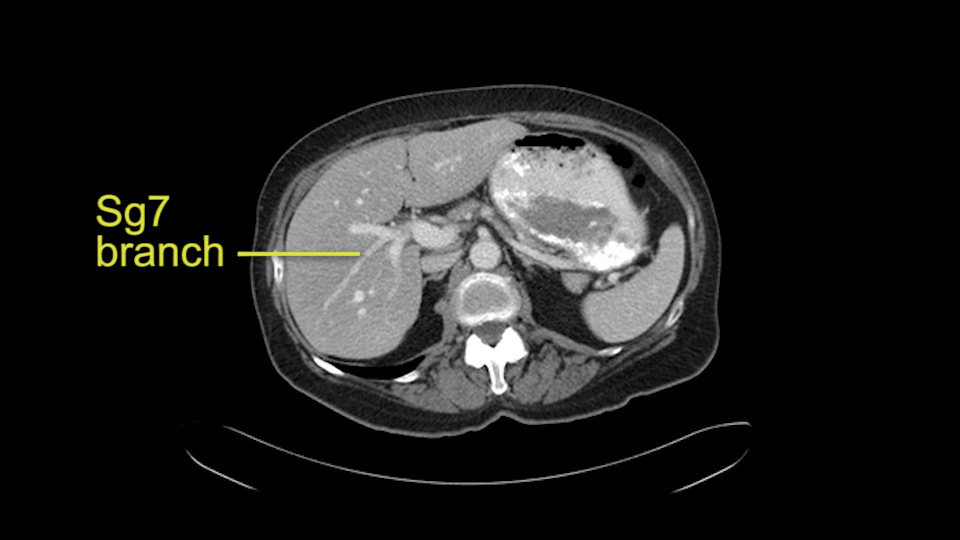

Sg 7 branch at right portal vein bifurcation

Divide bile duct in liver

This patient has an interesting minor anomaly with what looks like a Segment 7 portal vein coming off close to the bifurcation of the right portal vein but again if I was doing a right lobe which is my plan, this wouldn’t be an issue.

![[Sg7 branch]](jpg/preop_sg_moment5.jpg)

Finally the bile duct is divided in the liver. I can actually see this patient’s bile duct. It’s a bit dilated and she had cholecystectomy. I think we would divide the bile duct in the liver. It’s hard to anticipate from a CT scan what you’re going to see because you can’t actually see the bile duct very well on the average CT.

![[Sg7 branch]](jpg/preop_sg_moment6.jpg)

So overall I would plan to do a right hepatic lobectomy. The slowing down moments are the usual ones: carefully mobilizing the right lobe, not injuring the main hepatic veins or the vena cava, the right portal vein split, the length of the right portal vein. The rest looks very routine. The oncologic issue I’ve already decided I’m going to do a right lobe with the assumption that there is an intrabiliary metastasis somewhere near the origin of the right- the Segment 7 duct and probably close to the bifurcation of the main right bile duct so the best way to get a margin is to actually divide the right bile duct close to its origin the way you would normally do a right hepatic lobectomy.